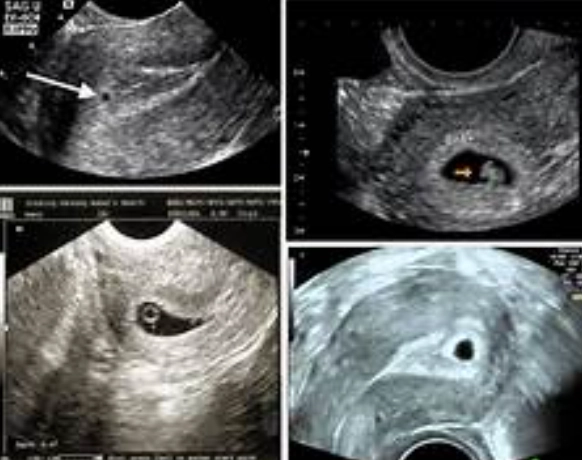

It's too early for a visible baby bump, obviously. Your uterus is about the size of a pear and is just beginning to soften. An ultrasound at this stage, if done, might only show the gestational sac—the small, fluid-filled structure that houses the embryo. You likely won't have your first prenatal appointment until you're 8-10 weeks along, so this first month is often a private journey of discovery between you, your body, and maybe a partner.